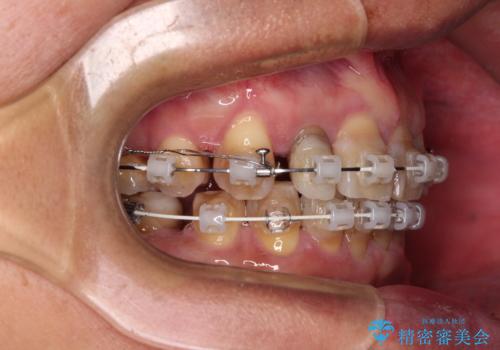

左右に骨格がずれて咬みにくい ワイヤー装置による抜歯矯正

- 骨格的な咬み合わせのズレ、前歯のデコボコとクロスバイトを気にして来院された患者様です。

全額的にデコボコが強いため、上下左右の小臼歯計4歯を抜歯し、ワイヤー装置による矯正治療を行うこととしました。

抜歯する歯の一部をセオリーである第一小臼歯ではなく、第二小臼歯にすることで、骨格的なずれをカバーするように計画しました。

小臼歯の抜歯する部位を選択したことで、安定した咬み合わせとなりましたが、第二小臼歯を抜歯した部分はスペースを閉じるのに長い期間を要しました。